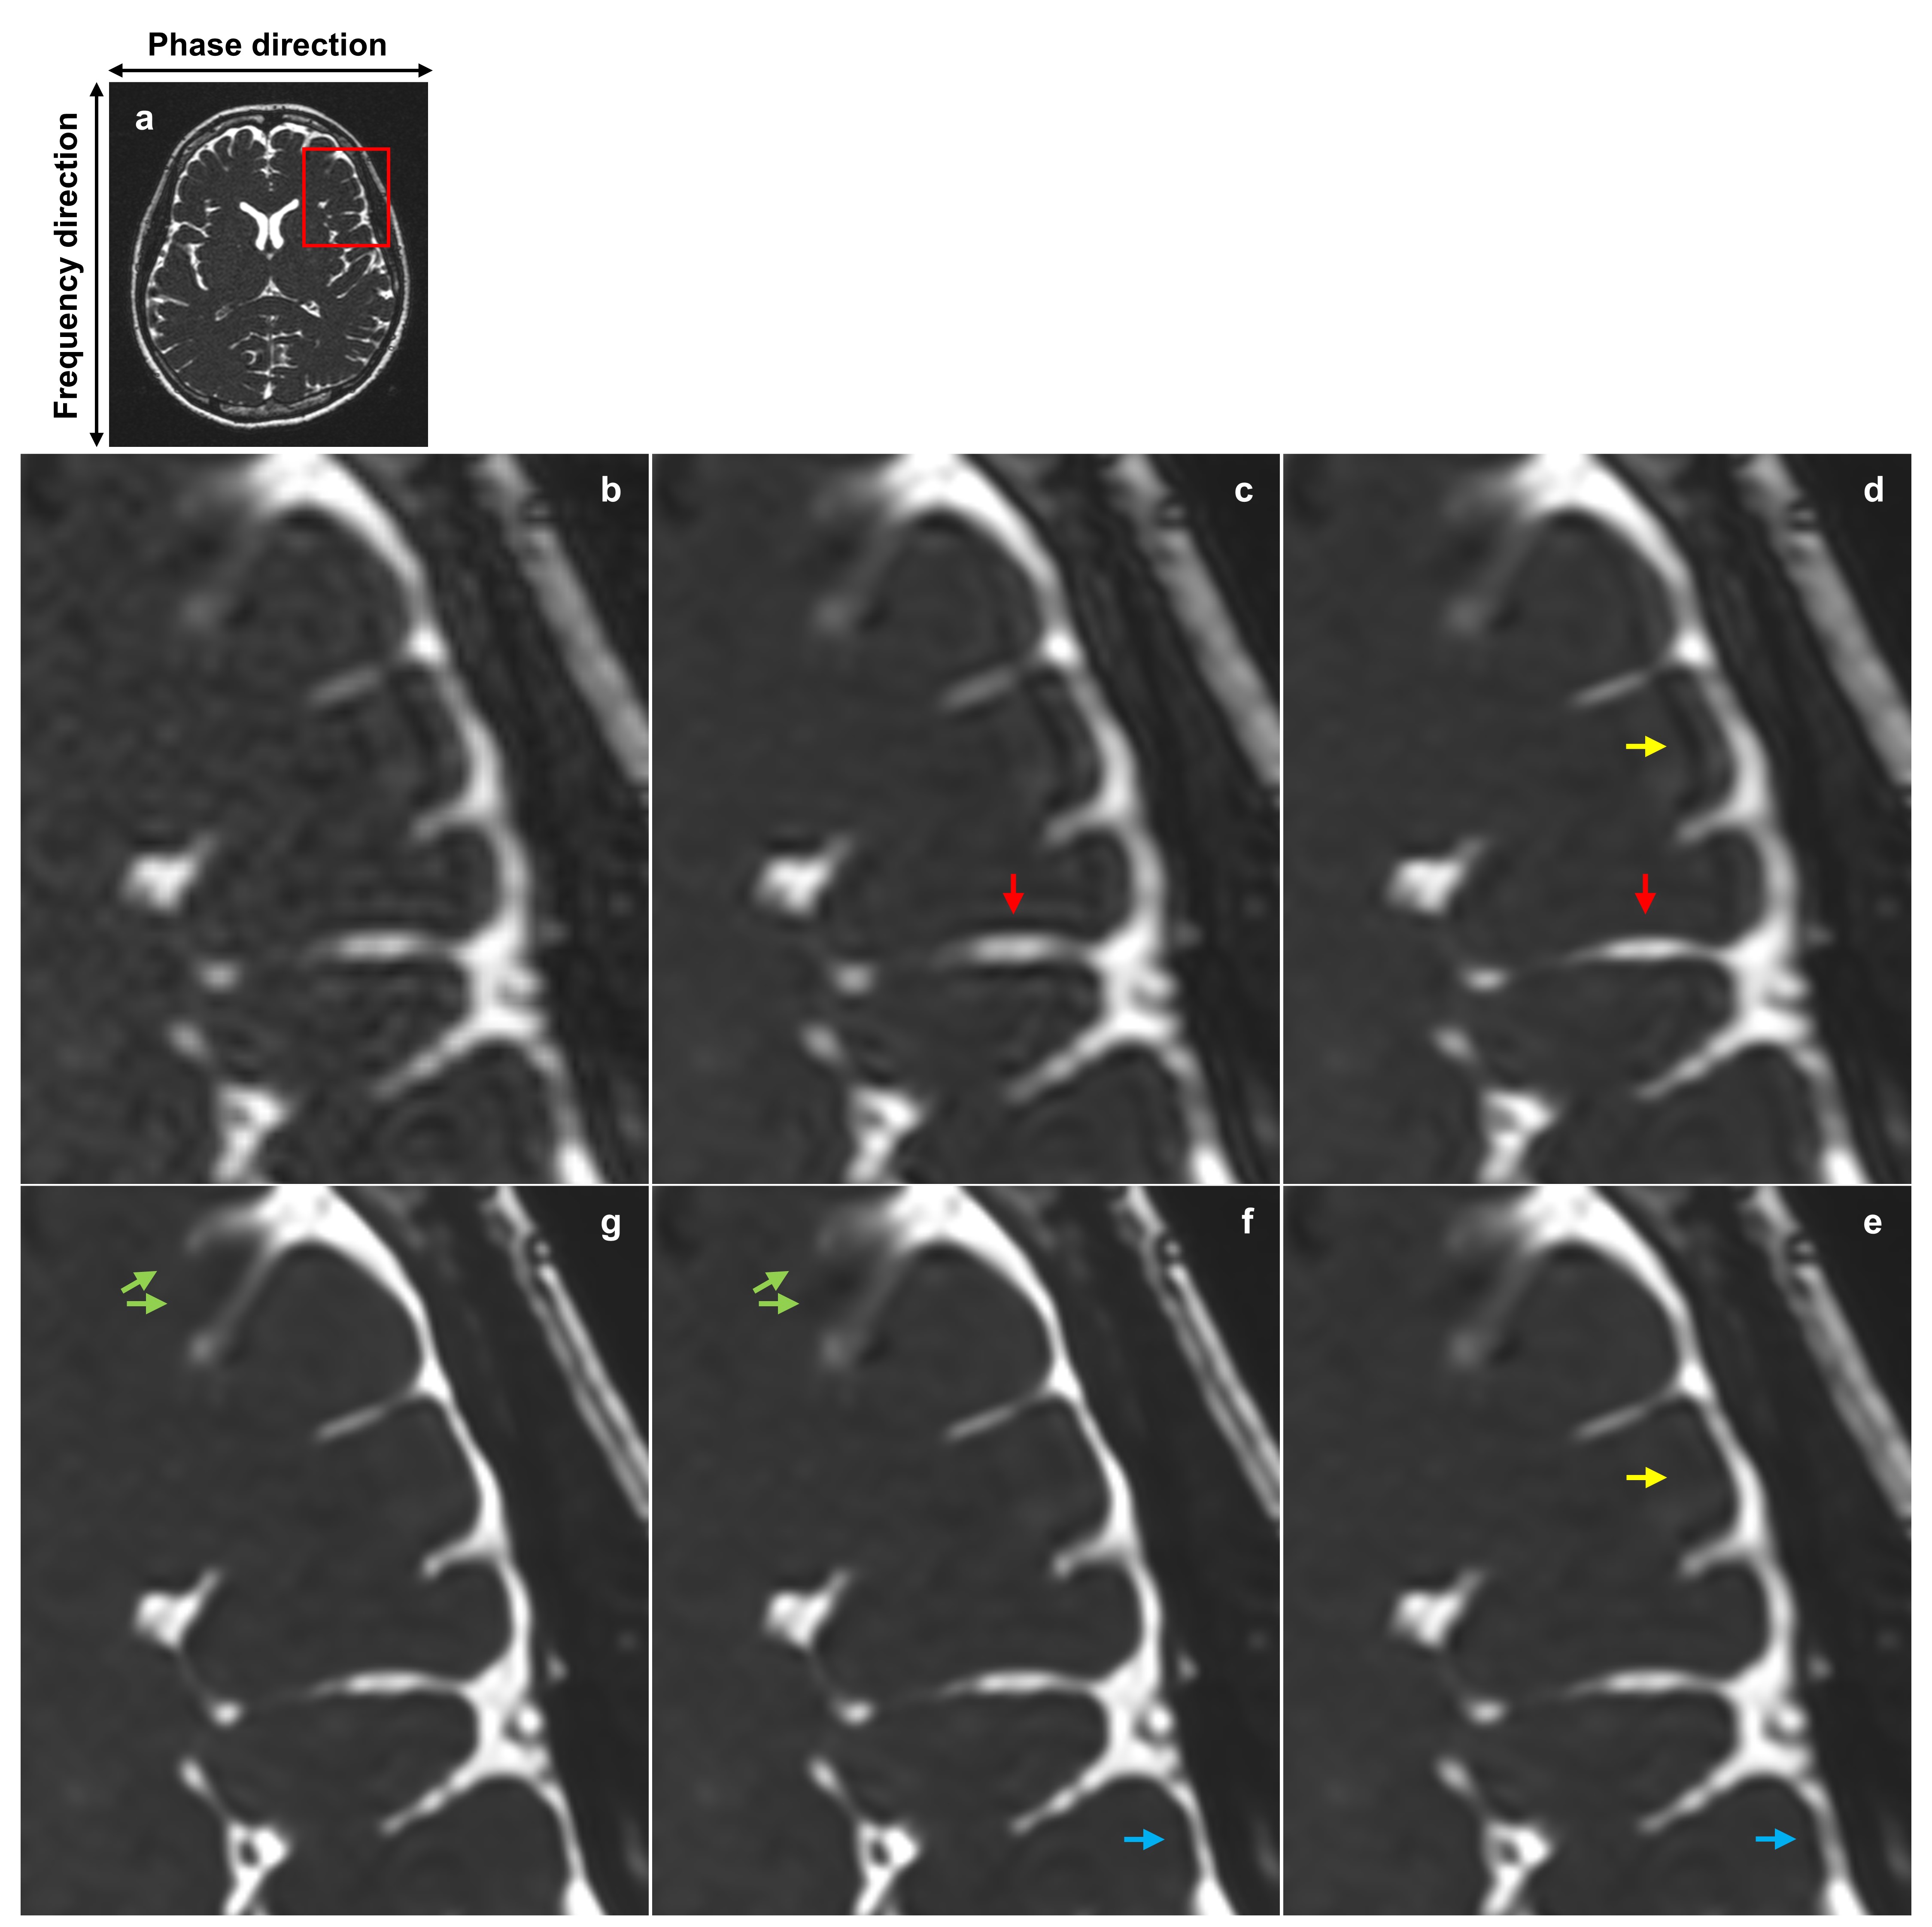

Figure 3 illustrates the change in image as each additional dimension is incorporated. Initially, the inclusion of the noise reduction dimension results in decreased noise without altering perceived resolution. The subsequent addition of the frequency kmaxsubscript𝑘𝑚𝑎𝑥k_{max} dimension enhances perceived resolution in frequency direction. Following this, including the phase partial Fourier dimension reduces partial Fourier induced blurring. Adding the phase kmaxsubscript𝑘𝑚𝑎𝑥k_{max} dimension further boosts apparent resolution in phase direction. Lastly, incorporating the slice kmaxsubscript𝑘𝑚𝑎𝑥k_{max} dimension diminishes image blurring caused by slice directional partial volume effects. Comparing the original image with the fifth reconstructed image, which includes all dimensions, confirms the multi-dimensional image improvement.

Refer to caption

Figure 3: Visual comparison between multiple DLR images, each adding a new dimension of improvement incrementally. (a) Shows the original image. Subsequent images are magnifications of the area marked by a red rectangle in (a): (b) Magnified area of the original image. (c) Noise reduction only, demonstrating decreased noise compared to (b) without a change in perceived resolution. (d) Includes enhancement in the frequency kmaxsubscript𝑘𝑚𝑎𝑥k_{max} dimension, improving perceived resolution in the frequency direction (red arrows). (e) Adds the phase partial Fourier dimension, reducing partial Fourier induced blurring (yellow arrows). (f) Incorporates the phase kmaxsubscript𝑘𝑚𝑎𝑥k_{max} dimension, boosting apparent resolution in the phase direction (blue arrows). (g) Final enhancement in the slice kmaxsubscript𝑘𝑚𝑎𝑥k_{max} dimension, reducing blurring due to slice directional partial volume effects (green arrows). Each of five DLRs was performed on the original image by adjusting contextual data, not by sequentially reprocessing previous DLR images. A comparison between (b) and (g) illustrates the simultaneous multi-dimensional enhancement of image quality. DLR, deep learning reconstruction.